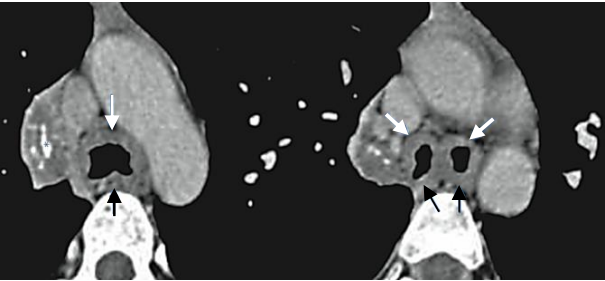

As imagens a seguir são sugestivas de: